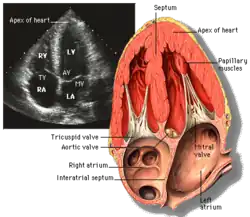

Transthoracic echocardiography (TTE) uses ultrasonic waves for continuous heart chamber and blood movement visualization. It is the most commonly used imaging tool for diagnosing heart problems, as it allows non-invasive visualization of the heart and the blood flow through the heart, using a technique known as Doppler.

Transesophageal echocardiography is an invasive procedure that involves inserting a flexible probe with an ultrasound transducer into the esophagus, providing closer access to the heart and surrounding structures.[5] This procedure allows for better imaging of the aorta, pulmonary artery, heart valves, atria, atrial septum, left atrial appendage, and coronary arteries. It can also be used during cardiac surgery to monitor the patient and assess the success of surgical interventions.[5] TTE can visualize non-dilated coronary arteries and measure coronary artery flow using harmonic imaging, contrast agents, and high-frequency transducers. This noninvasive and low-cost method can help diagnose and manage patients with suspected or confirmed CAD by demonstrating pathologic coronary artery flow patterns at rest and with pharmacological stress.[6]